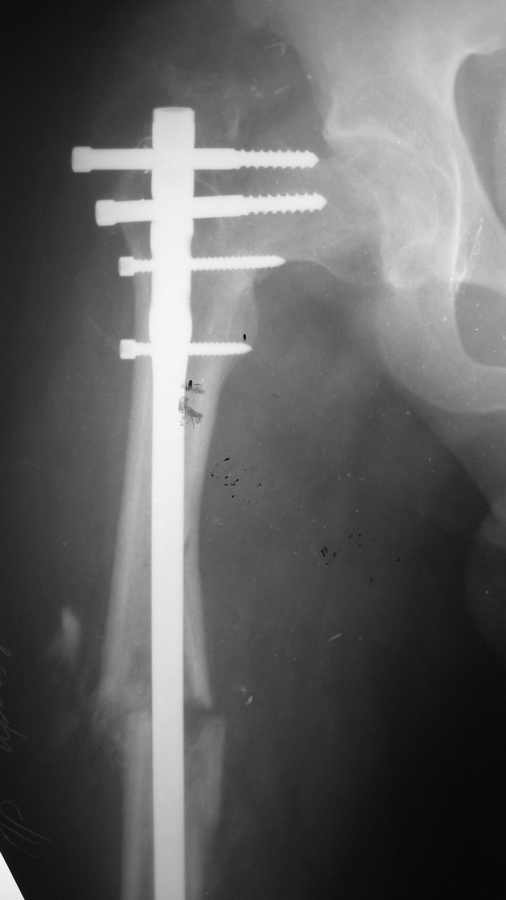

25 октября 2008 вследствие ДТП политравма (мотоциклист): оскольчатый диафизарный перелом правой бедренной кости + чрезвертельный перелом правого бедра ( был диагностирован во время операции, был без смещения).

По скорой помощи через 6 часов после аварии произведено оперативное лечение: интрамедулллярный остеосинтез правого бедра + фиксация чрезвертельного перелома 3-мя винтами. Металлоостеосинтез голеностопного сустава слева, пятка не оперировалась.

При контрольной рентгенографии через 1 месяц отмечено смещение в области чрезвертельного перелома,варусная деформация.